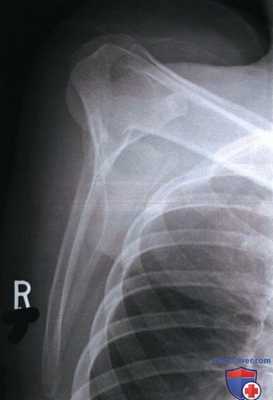

РИСУНОК 3 Рентгенограмма лопатки в ПЗ проекции без отведения плеча. РИСУНОК 4 Рентгенограмма лопатки в ПЗ проекции с недостаточной ретракцией плечевого сустава. РИСУНОК 5 Рентгенограмма лопатки в ПЗ проекции: перелом.

а) Отведение плечевой кости. Плечевая кость отводится в плечевом суставе при ротации лопатки вокруг грудной клетки. Отведение плеча на две трети происходит за счет движения в плечевом суставе, и на одну треть — за счет движения лопатки. При отведении плеча латеральный край лопатки выдвигается из-под грудной клетки, вследствие чего суставная впадина лопатки смещается вверх. Поскольку отведение плеча на первые 60° обеспечивается преимущественно плечевым суставом без сопутствующего движения лопатки, то для отображения всего латерального края лопатки без наложения на него грудной клетки, как и для отображения надостной ямки и верхнего угла лопатки без наложения ключицы, плечевую кость следует отвести как минимум на 90°. Если плечевая кость отведена меньше чем на 60°, нижнелатеральный край лопатки будет накладываться на грудную клетку, а ключица — на верхний угол лопатки (рис. 3).

б) Ретракция плечевого сустава. Если рентгенография лопатки в ПЗ проекции выполняется без отведения плеча на исследуемой стороне, то тело лопатки будет располагаться под углом 35-45° к ПИ, что приведет к его поперечному проекционному укорочению. Чтобы уменьшить выраженность поперечного проекционного укорочения тела лопатки и улучшить его визуализацию, рентгенографию выполняют в положении лежа на спине с отведенной плечевой костью, согнутым локтевым суставом и супинацией кисти за счет наружной ротации плеча (рис. 4).

При отведении плечевой кости лопатка скользит вокруг поверхности грудной клетки, вследствие чего из-под нее выдвигаются нижний угол и латеральный край лопатки. Сгибание локтевого сустава и супинация кисти приводят к ретракции плечевого сустава за счет давления на латеральный край тела лопатки, благодаря чему он смещается назад, что позволяет уменьшить выраженность проекционного укорочения тела лопатки. Чтобы обеспечить максимальную ретракцию плечевого сустава за счет силы тяжести, рентгенографию выполняют в положении лежа на спине. О недостаточном отведении плеча и недостаточной ретракции плечевого сустава свидетельствуют избыточное проекционное укорочение тела лопатки и визуализация суставной впадины лопатки почти в торец (см. рис. 4).